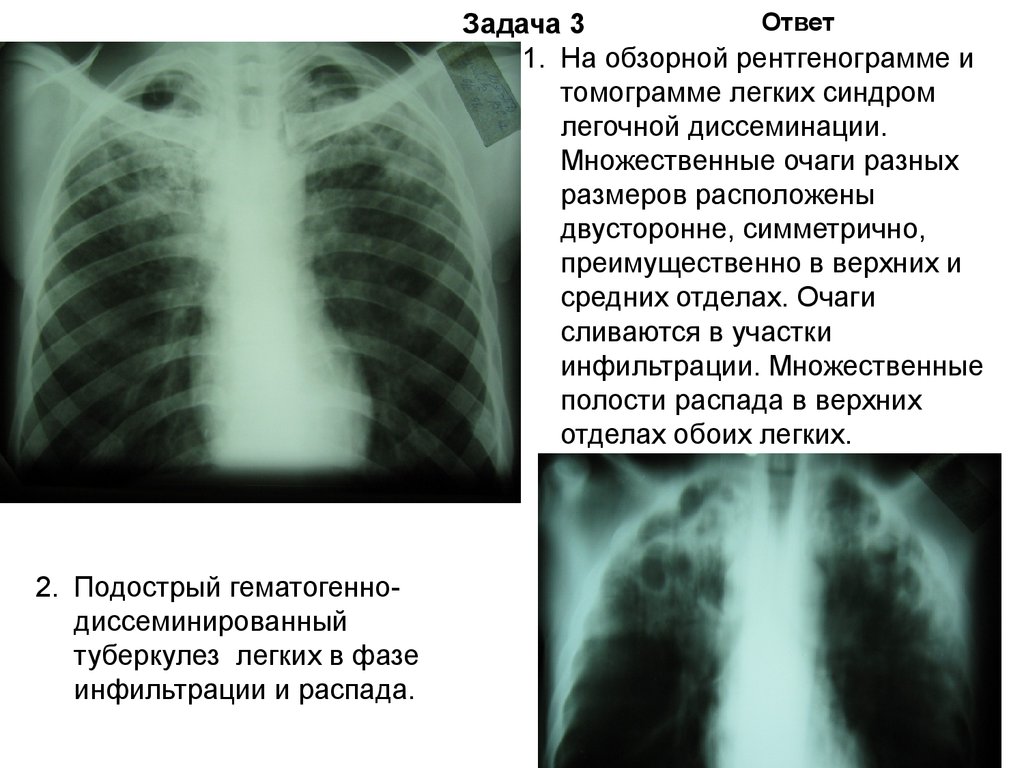

Иллюстрации по теме очагового и инфильтративного туберкулеза